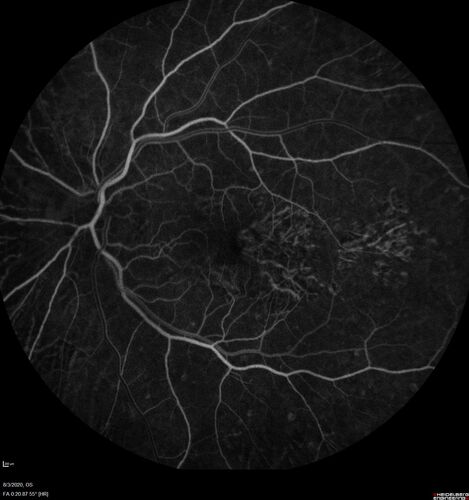

Dry AMD geographic atrophy and cystoid macular edema

79 year old vision is in for a checkup with no visual complaints in the left eye.  This is her better eye.  VA 20/200 OD, 20/50 OS.  3 years ago she had a CRVO in the left eye.  She is also diabetic for 20 years, has carotid insufficiency and anemia.  Left eye shows CME.  This was not treated and the vision improved to 20/40 over the next year although mild edema persisted.